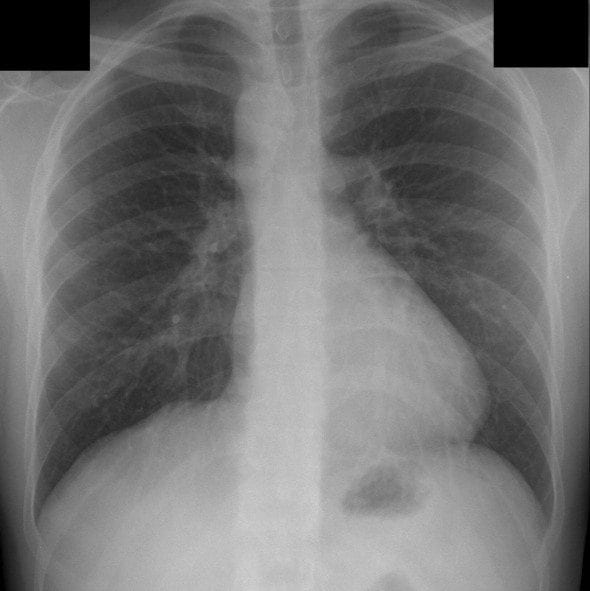

A 26 year-old man presented to the ED with chest pain, He tripped on some steps and the right-side of his chest collided with the handrail.This is his chest radiograph:

There is a right-sided aortic arch.

- The trachea is deviated to the left of the midline rather than the right.

- There is no evidence of traumatic injury or situs inversus.